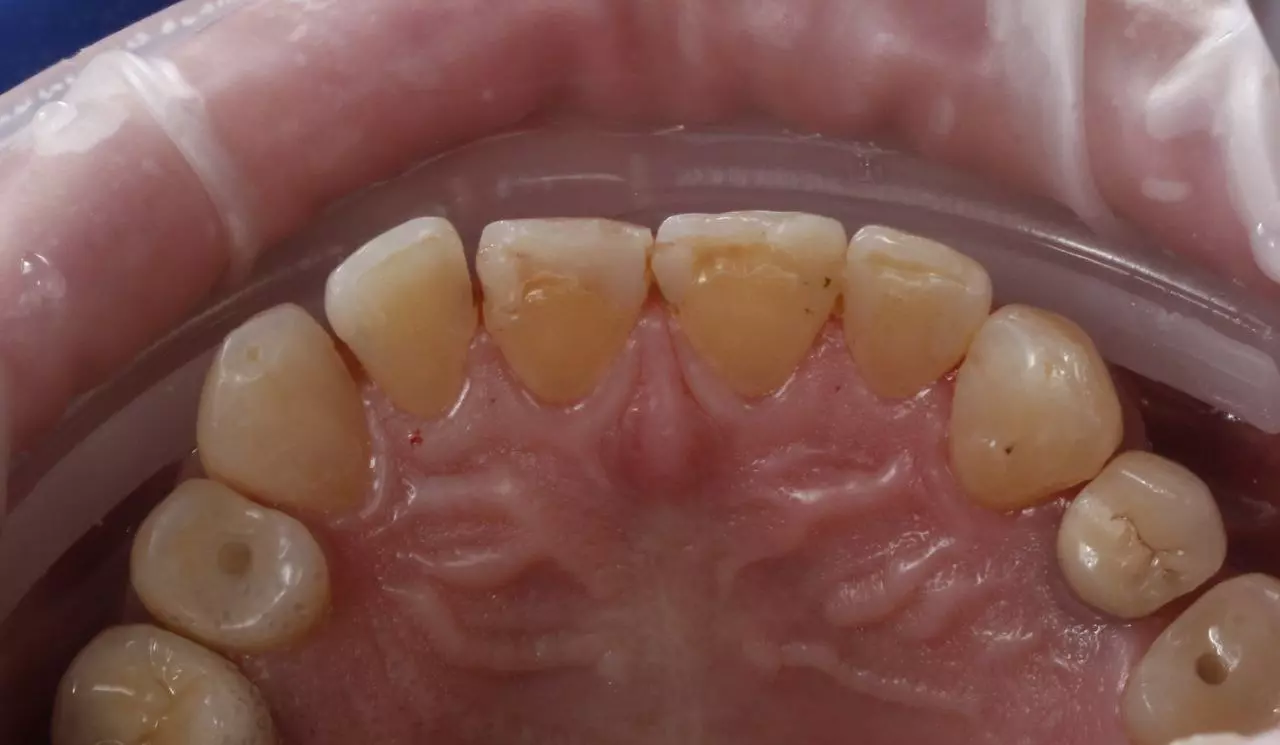

Художня реставрація 13.12.11.21.22.